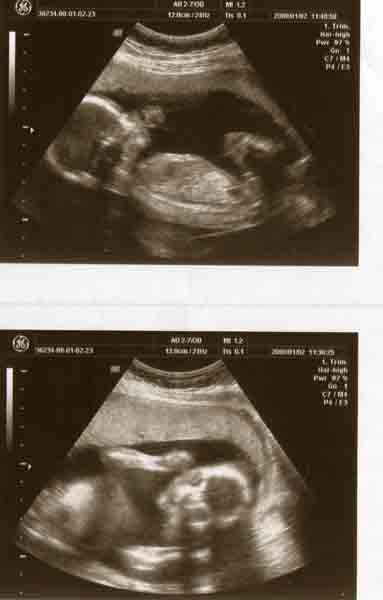

Íme 2 bemutatkozó fotó a kicsikről:

Kép Kép

Fanni

Fanni, Milán, Márk